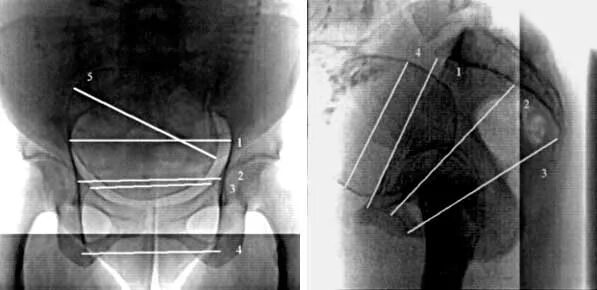

Делала рентген при беременности